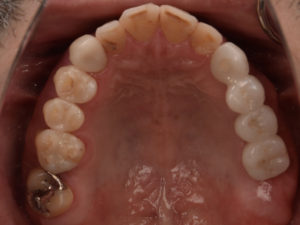

【歯科医が認めるインプラント治療】九州の歯科医がインプラントオペの患者として来院されました。

当院で2019年9月に行った公開オペの患者さんとして九州で開業されている鶴田先生がはるばる来られました。初診時の状態です遠方からのご来院ということもあり、インプラントのオペの直後に仮歯を装着する「即時…